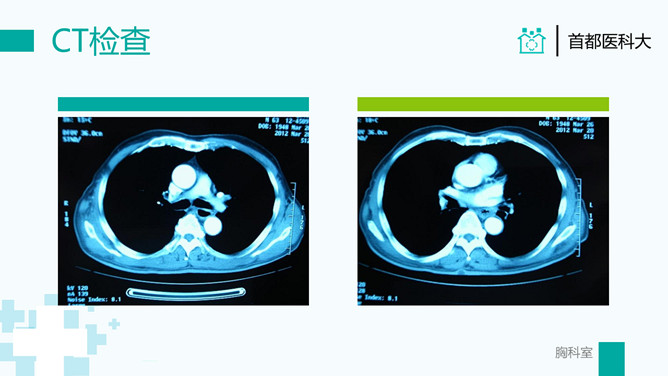

疑难病例讨论病例分析PPT模板。一套病例分析病例讨论通用幻灯片模板,简洁清新绿色主色调,医生背景。